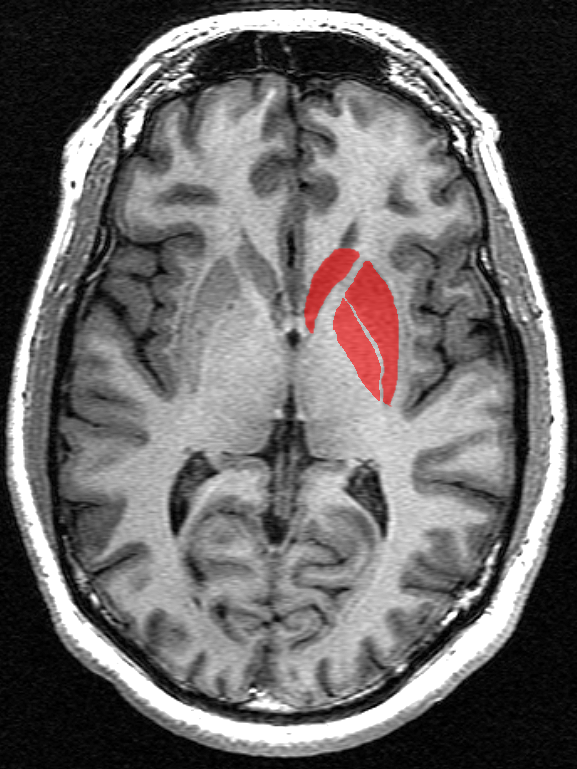

Was wissen wir also über das, was im Verlauf der Huntington-Erkrankung im Gehirn passiert? Sie wissen wahrscheinlich, dass sich die HK am meisten auf eine Gehirnregion namens Basalganglien auswirkt. Die Basalganglien sind eine Gruppe von miteinander verbundenen Hirnregionen, die sich tief im Zentrum des Gehirns befinden und zusammen Bewegungen und Motivation eines Menschen steuern.

Unter den Regionen, aus denen sich die Basalganglien zusammensetzen, befindet sich das Striatum. Wenn man grob über die Veränderungen im Gehirn durch die HK spricht, spricht man meist über den am häufigsten vorkommenden Zelltypen im Striatum. Diese Zellen werden mittelgroße dornige Neurone genannt und sind aus bisher unerfindlichen Gründen besonders empfindlich, wenn eine Person die Huntington-Mutation in sich trägt.

Lange bevor wir verstanden haben, wie die dornigen Neurone aussehen oder wie sie kommunizieren, haben Anatomen im frühen 20. Jahrhundert festgestellt, dass irgendetwas im Striatum von HK-Patienten nicht richtig ist. Durch post mortem-Vergleich (nach dem Tod) von Gehirnen von HK-Patienten und gesunden Menschen war offensichtlich geworden, dass das Striatum geschrumpft war. Statt einer Art Beule, die diese Struktur normalerweise definiert, sah es eher aus wie ein platter Ballon. Da diese Information auch ohne Hilfsmittel deutlich sichtbar war, rückte das Striatum schnell in den Fokus der HK-Forschung.

Heute wissen wir, dass eine der Hauptaufgaben der dornigen Neuronen im Striatum ist, inhibitorische Signale an Zellen zu senden, die Bewegungen steuern, um sie ruhig zu stellen. Ansonsten würden die sehr aktiven, erregenden Zellen ständig ihre Nachrichten an andere Regionen aussenden, wie zum Beispiel: „Bewege Deine Muskeln jetzt!“ Wenn nun viele dornige Neuronen verloren gehen bedeutet dass, dass die erregenden Zellen mehr Signale aussenden können. Dies ist eine Möglichkeit, die Bewegungssymptome bei HK-Patienten zu erklären. Andere Symptome wie Depressionen, Persönlichkeitsveränderungen, Schlafprobleme oder Ängstlichkeit lassen sich dadurch aber nicht wohl nicht erklären.